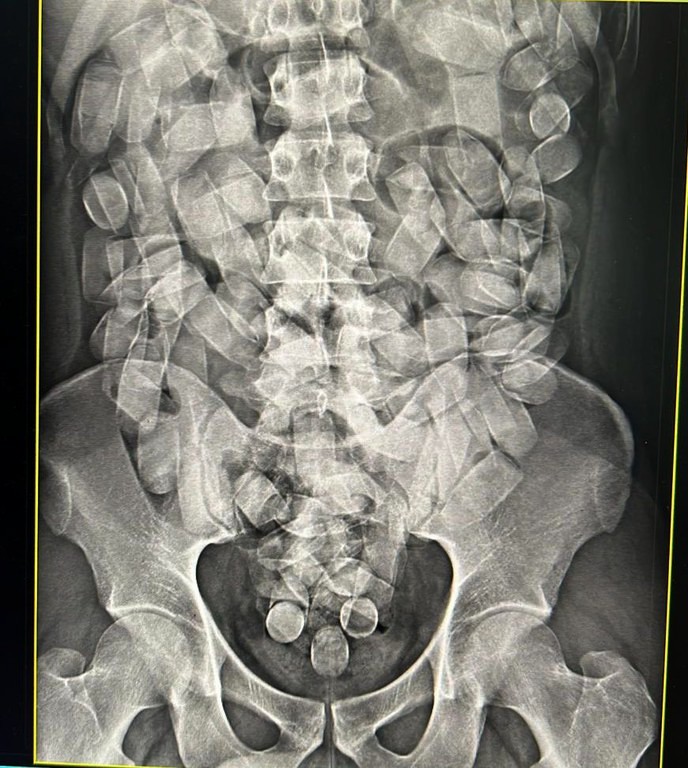

Neste domingo, 19/05, policiais federais realizaram a prisão em flagrante de um homem quando tentava embarcar no aeroporto de Corumbá/MS transportando cocaína, em cápsulas, em seu estômago.

O passageiro, que tinha por destino São Paulo, transportava 125 cápsulas ingeridas de cocaína. Esta é a segunda prisão nesta semana, no mesmo aeroporto, realizada pela Polícia Federal.